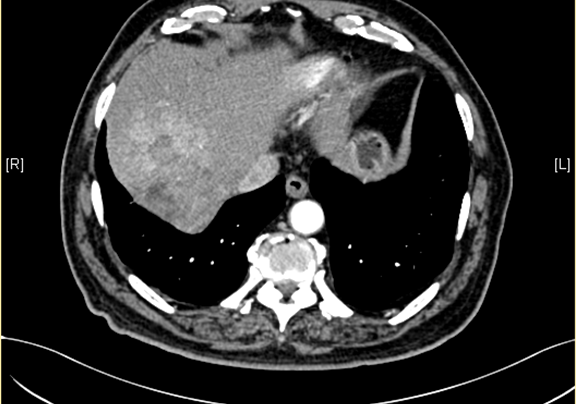

下腹部增强CT示:肝右后叶上段占位,肝癌可能性大;右侧肾上腺占位,不除外转移瘤。

术前CT检查:

动脉期

静脉期

平衡期